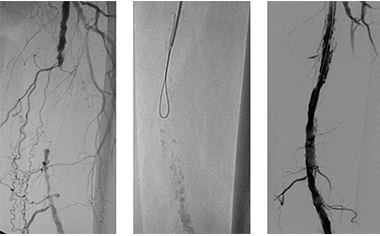

Reduced circulation in leg: Cramp like pain in the leg muscles that comes on walking (not only on standing), particularly while going up stairs or slopes or on walking fast, is relieved with rest and recurs on resuming of walking.

Poor circulation in leg: Burning pain in the feet or toes present on lying flat in the bed and is relieved by hanging the leg from the edge of the bed or in the dependent position. Gangrene of the digits or limbs. Non-healing ulcers - Wounds that do not heal.